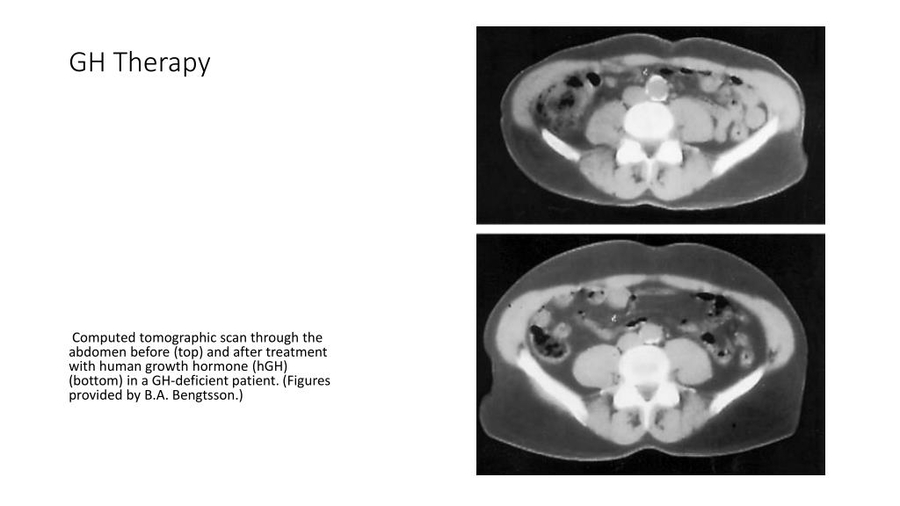

Scientists reported a significant reduction in joint pain, and about 14 degrees increase in mobility on average after 5-12 weeks of weekly intra-articular Clinical evidence suggests that systemic HGH therapy may also help heal injuries in tissues with quickly dividing cells, such as the skin and the gastrointestinal